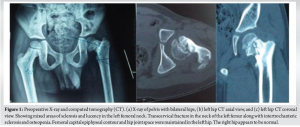

A 7-year-old boy presented with left hip pain for 1 year without any history of trauma or systemic illness. Antenatal and birth history were uneventful. Developmental history was normal. Movements of the left hip were restricted (especially internal rotation), with the left femur shortened by 2 cm. The Trendelenburg test was negative. Initial X-ray and computed tomography (CT) showed a left neck of femur transcervical fracture with a mixed area of lucency and sclerosis (predominant) in the femoral neck (Fig. 1).

Post-operatively, the patient was mobilized after 6 weeks of bed rest. The patient was regularly followed up on an outpatient basis, and serial X-rays demonstrated a maintained NSA (Fig. 6). On April 13, 2023 (8 years post-operative), the patient did not have any complaints of pain. Left hip movements were full, except internal rotation, which was restricted terminally. The left femur was shortened by 1 cm. The Trendelenburg test was negative. The patient mobilized, squatted, and moved his left hip pain-free (Fig. 7). Eight years post-operative X-ray (Fig. 8) showed left NSA in the acceptable range (129°) with shortening of the femoral neck. There was no evidence of the mixed, predominantly sclerotic lesion in the femoral neck, which was evident in the presenting X-ray.

Coxa vara refers to a pathological reduction in the NSA with an increase in femoral retroversion. Coxa vara can be secondary to trauma, infections, or metabolic disorders; associated with congenital femoral deficiency; or developmental (DCV), resulting from disruptions during the growth and maturation of the hip joint. This condition alters the biomechanics of the hip joint, resulting in limping, hip instability, pain, and limited mobility. With an estimated incidence of 1 in 25,000 live births, DCV is still a rather rare condition. Around 30–50% of patients have bilateral involvement [2]. Coxa vara is also associated with acetabular dysplasia [6]. The main controversy in the literature concerns the etiological classification of this condition. Broadly, the primary forms, with no other cause, are considered to be either congenital or developmental, while those with an obvious underlying cause are acquired [1]. Almond et al. established that infantile coxa vara is a familial condition [7]. Increased intrauterine pressure, localized dysplasia, metabolic abnormalities, vascular insult, and non-specific metabolic abnormality are a few hypothetical theories for primary coxa vara [1]. DCV is diagnosed with radiographs showing a decreased NSA (typically <120°), a vertical physis, a triangular metaphyseal fragment in the inferior femoral neck with an inverted “Y” shape, a shortened femoral neck (coxa breva), femoral retroversion, and often mild acetabular dysplasia [1,6]. The indications for surgical treatment of coxa vara are Hilgenreiner-epiphyseal angle >60° or HE angle 45–60° with progression of the deformity and Trendelenburg gait [1,2,3,4]. This case is an unusual presentation of DCV due to the absence of the classic triangular metaphyseal fragment in the inferior aspect of the femoral neck, which questions the very diagnosis of DCV. The pre-operative X-rays clearly demonstrated a mixed (predominantly sclerotic) lesion in the proximal femur metaphysis (femoral neck), which brings up the suspicion of a tumor or fibrous lesion. Pre-operative CT and MRI showed no evidence of metabolic bone diseases or a tumor. The presence of a pathological left neck of femur fracture warranted surgical fixation, and hence, left proximal femur lateral closed wedge osteotomy with proximal femur locking plate was done on August 22, 2013. Intraoperative biopsy sent for histopathological examination was inconclusive. The initial surgery was performed with screws that did not cross the proximal femoral physis, as this physis contributes approximately 15% to the overall growth of the femur [5]. However, the decision to preserve physeal growth led to recurrence of coxa vara due to inadequate stability (screws not crossing the physis) [8] and probably due to the stress riser effect of the tip of the screws inserted into the neck. In the second surgery, the lag screw of the DHS was placed across the physis, prioritizing mechanical stability over growth preservation. In addition, as the patient ages, the contribution of the proximal femoral physis to femoral growth decreases, while the distal femoral physis takes on a greater role, accounting for approximately 90% of femoral growth by 16 years of age [9]. Hence, the second procedure-medial open wedge osteotomy and fixation with pediatric DHS (with lag screw crossing the physis) corrected the deformity. Over a period of 8 years, the patient improved symptomatically, even though true shortening of the femur (1 cm) was present. HE angle is the most important prognostic factor for recurrence [2,3,4,10], and in this case, HE angle post-operatively was 32 and 36 degrees after the first and second procedure, respectively (which falls under the recommended reference value of 38° or less [3,11]). The NSA was also restored post-operatively in both procedures [12]. The X-ray taken 8 years post-DHS fixation (Fig. 8) showed shortening of the left femoral neck, which was due to the lag screw of the DHS crossing the physis. The X-ray (Fig. 8) clearly demonstrated the disappearance of the mixed (predominantly sclerotic) lesion in the proximal femur metaphysis, which was clearly evident in the presenting X-ray and CT. Yanagawa et al. (2001) identified several benign bone lesions with potential for spontaneous regression, including bony exostosis, non-ossifying fibroma, and osteoid osteoma [13].